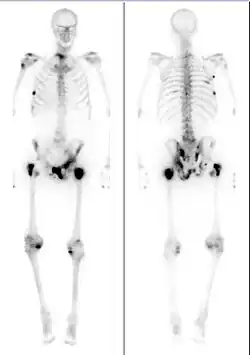

Medical image showing a man's skeleton with several dark spots along the bones

Bone scintigraphy scan of a man with metastatic prostate cancer. Dark spots indicate metastases along the pelvis, ribs, and shoulder.